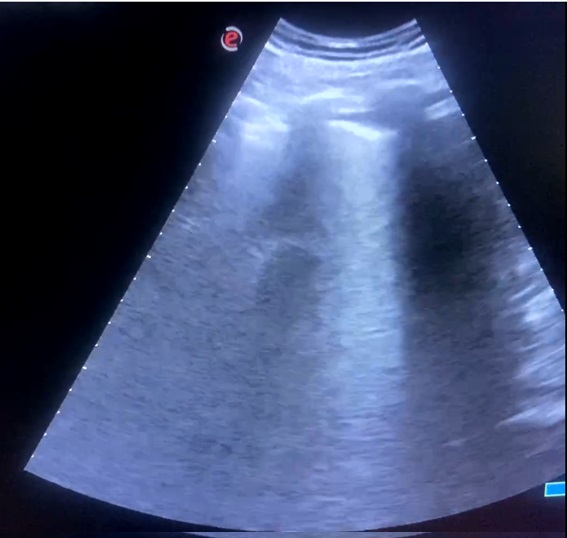

Ecografía pulmonar en AP:

«Líneas B en campos pulmonares izquierdos y consolidación pulmonar en base derecha con mínimo derrame pleural, compatible consolidación infecciosa vs tromboembólica.

Se amplía estudio con ETT que no muestra signos de sobrecarga de ventrículo derecho, y eco Doppler de MMII sin hallazgos de TVP con venas safenas y femorales permeables y colapsables».